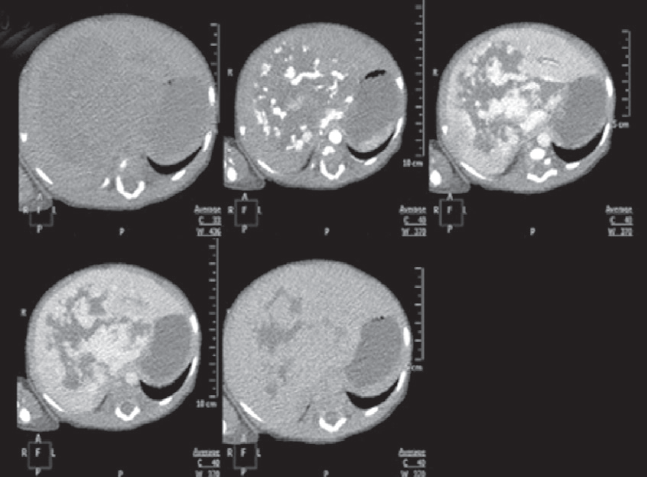

Проведено обследование: УЗИ органов брюшной полости — визуализируется объемное образование с кровотоком, занимающее всю правую долю печени. МСКТ брюшной полости с контрастным усилением — выявлено гигантское сосудистое образование печени срединного расположения (рис. 8).

Рис. 8. Аксиальные компьютерно-томографические снимки во все фазы контрастирования

Fig. 8. Axial CT images in all phases of contrast

При контрольном обследовании в возрасте 3 мес. на УЗИ признаков прогрессирования образования печени не выявлено. МСКТ органов грудной клетки и брюшной полости с в/в контрастированием: в легких без очаговых и инфильтративных изменений, отмечается умеренное уменьшение объема образования, уменьшение диаметра и количества сосудов в центральных отделах образования (рис. 9).

Рис. 9. Компьютерно-томографические снимки брюшной полости в различных плоскостях и фазах контрастирования, контроль в 3 месяца

Fig. 9. CT images in various planes and contrast phases, control at 3 months

При контрольном обследовании в возрасте 8 мес. по МСКТ отмечается продолженное уменьшение размеров образования на 65 % от первичного объема.